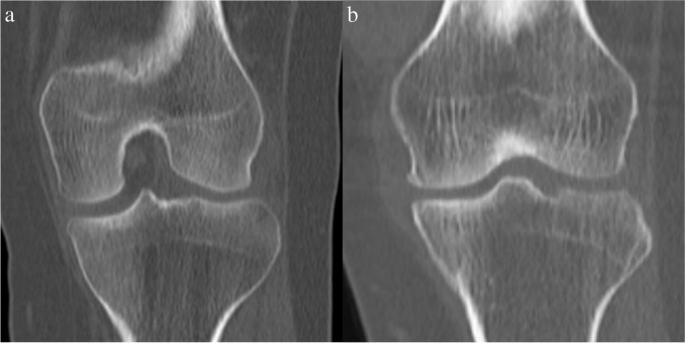

• X-rays: To identify changes in bone structure and joint space narrowing.

• MRI: To examine soft tissue damage, including ligaments and cartilage.